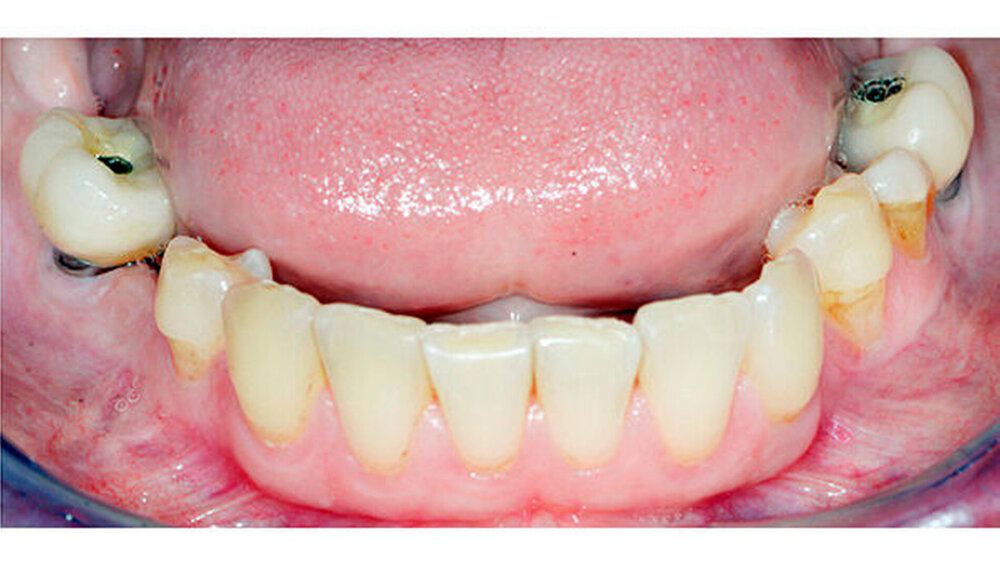

Trotz dieser Extrembedingungen gelang es dem erfahrenen Stuttgarter MKG-Chirurgenteam um Prof. Dieter Weingart durch Anhebung des Nasenbodens und Einbringung von Eigenknochen in dieser Region ein Fundament für eine neue Zahnversorgung mit Implantaten zu schaffen. Über die Jahre konnten die Seitenzähne zunächst gehalten werden. Im Laufe der Zeit zeigte sich aber, dass die Wurzeln nur noch auf dem Zahnfleisch auf lagen und lediglich durch eine Verblockung der Zähne hielten.

Daher mussten auch die Seitenzähne im Oberkiefer und teilweise im Unterkiefer entfernt und mit Implantaten ersetzt werden. Dies erfolgte unter anderem unter Einsatz von navigationsgestützten Techniken. Im Seitenzahnbereich des Oberkiefers musste eine Sinusaugmentation mit Knochen durchgeführt werden. Dabei wurde mit allen Vorsichtsmaßnahmen vorgegangen, die nach einer Bestrahlung des Knochens zu treffen sind.

Bis zur letztendlich verbleibenden festsitzenden Versorgung der Implantate mit Kronen musste die Patientin eine herausnehmbare Prothese mit Gaumenabdeckung tragen, die sie als junge Mutter sehr belastete. Umso glücklicher ist die Patientin nun über ihre vollständige prothetische Rehabilitation.